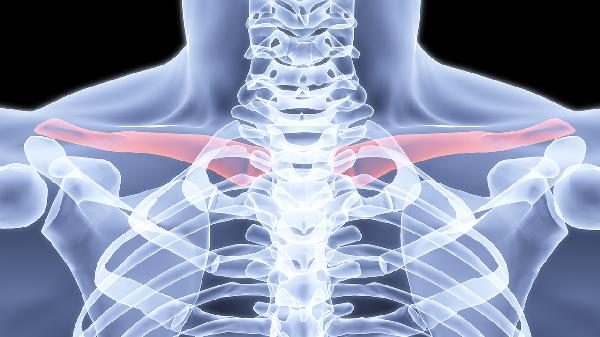

锁骨骨折错位严重时是否适合保守治疗需根据错位程度和并发症风险综合评估,主要考虑因素包括骨折端移位距离、是否合并血管神经损伤、患者年龄及功能需求。保守治疗适用于移位小于锁骨宽度1.5倍、无重要结构压迫的闭合性骨折,常用方法有八字绷带固定、锁骨带制动及康复训练。

骨折端横向移位超过锁骨宽度1.5倍或成角大于30度时,保守治疗易导致畸形愈合。此时骨折断端接触面积不足,局部血运破坏严重,骨痂形成缓慢,可能遗留肩关节功能障碍。儿童青枝骨折或老年人低需求活动者,可适当放宽指征。